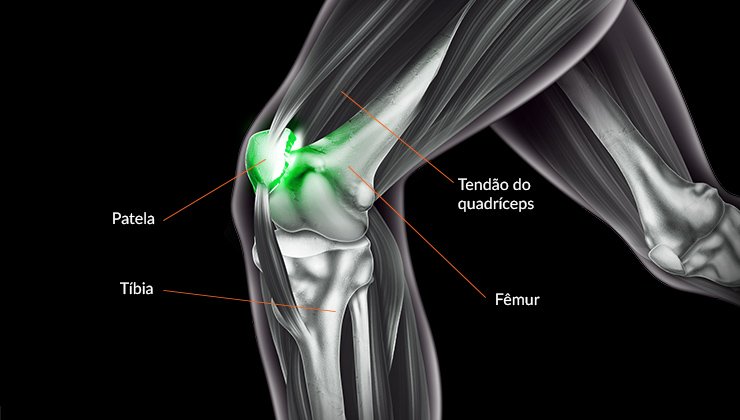

Assim sendo, a tendinite no joelho ocorre devido ao desgaste ou sobrecarga nos tendões, afetando principalmente atletas e pessoas que realizam atividades repetitivas. Com efeito, a dor costuma ser intensa e pode prejudicar atividades básicas, como subir escadas ou caminhar. Dessa forma, um tratamento adequado garante a recuperação da função articular e a prevenção de lesões crônicas.

De fato, a primeira etapa inclui repouso, fisioterapia, uso de medicamentos anti-inflamatórios e exercícios de fortalecimento. Além disso, é provável que a correção de postura e o ajuste da rotina de treinos sejam recomendados. Ao propósito, recursos como alongamentos direcionados auxiliam na melhora da flexibilidade, enquanto terapias manuais aceleram a recuperação. Por certo, em casos de maior complexidade, procedimentos semelhantes à Cirurgia artroscópica para instabilidade do ombro mostram como a tecnologia minimamente invasiva pode ser adaptada a diferentes articulações.

Em primeiro lugar, quando os sintomas persistem por longos períodos, a avaliação médica torna-se indispensável. Do mesmo modo, pacientes com histórico de lesões devem procurar especialistas para diagnóstico detalhado. Por consequência, ignorar os sinais pode agravar o quadro, levando a rupturas ou à necessidade de cirurgias mais complexas. Em contrapartida, o acompanhamento regular com um Ortopedista especialista em ombro demonstra como o conhecimento aprofundado em articulações pode ser aplicado também ao tratamento dos joelhos.